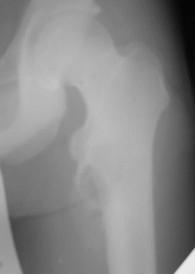

Здравствуйте ,уважаемые коллеги.Обратился парень 15ти лет с жалобами на боли в левом

коленном суставе. При обследовании обнаружена опухоль в в/з левой бедренной кости.

Проведено КТ заключение( остеохондрома) Подскажите пожалуйста, стоит ли сделать биопсию

перед операцией .Кокой операционный доступ и технику операции Вы посоветуете. С уважением

Игорь.

Имя     : IMG_1693.jpg